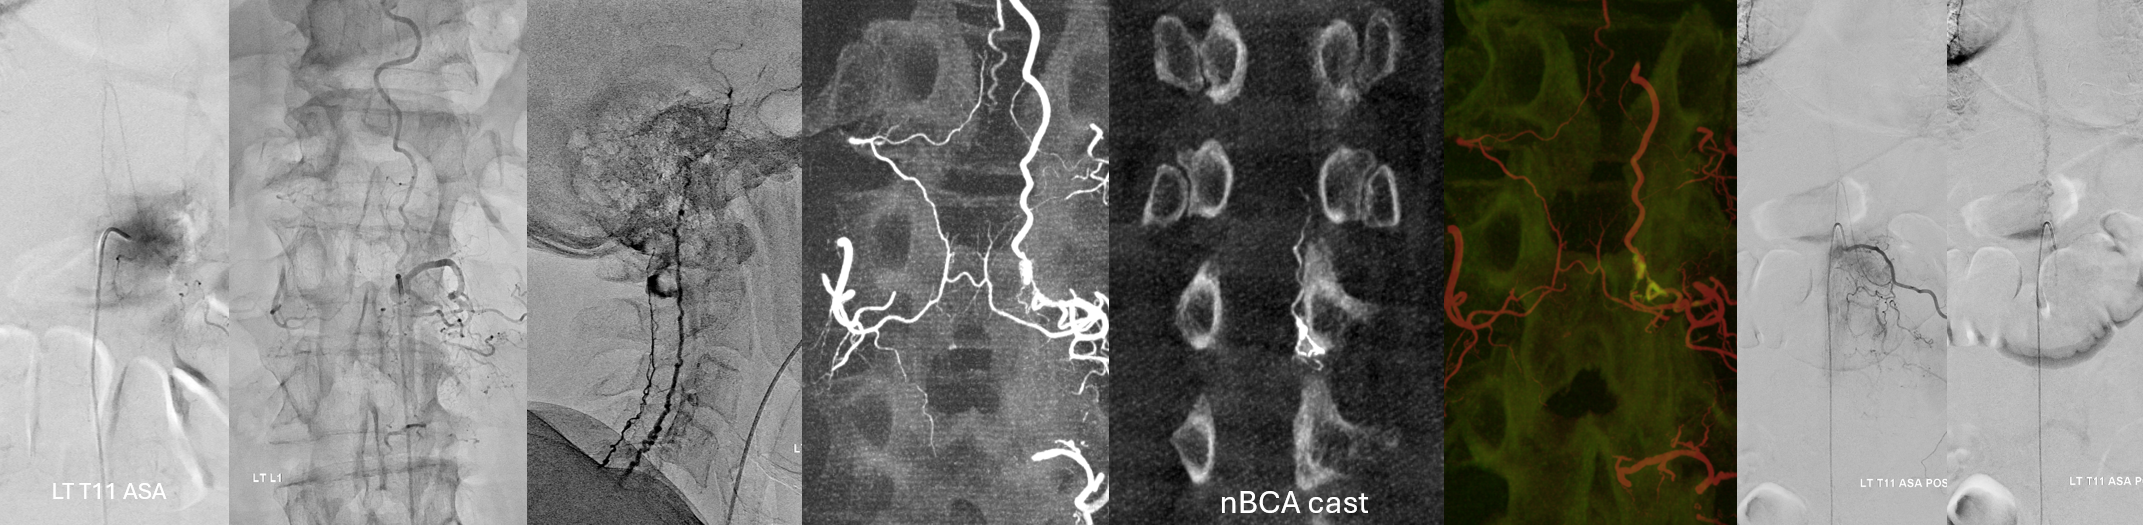

Fistula at left L1

Now to treatment. Hands are raised to get optimal Cone Beam CT view of the fistula (see Cone Beam CT Comprehensive Section, particularly Spinal CBCT Page, on details of how to do this). In this case, we do a dual volume 7 second unbinned “micro” acquisition, with injection of 100% contrast at 1 cc/second for 10 seconds with 3 second delay. Reconstructions are MIP and VR

VR

Headway duo near fistula. There are several other inflows, and the position is not optimal

Below is a better position. The fistula is at the level of the ball of vessels above the microcatheter tip. Several tributaries are present, which is not great, as they will tend to polymerize nBCA before it reaches the vein. Fortunately the radicular venous segment is long, before it reaches cord surface veins, so there is a lot of safety. This is not the case with upper thoracic fistulas, and we don’t want to spill glue into cord surface veins. It promotes thrombosis, which is erroneously known as the Foix-Alajouanine syndrome. The actual syndrome was described by Foix and Alajouanine as the clinical end stage of untreated spinal dural fistulas — ascending paralysis, followed by respiratory dysfunction, aspiration, and death. It was not an iatrogenic problem. The name was adopted to describe post-treatment acute deterioration due to thrombosis of enlarged cord veins after closure of the fistula and reduction of venous flow, in part because clinical presentation is comparably horrible. Typically happens some 6-12 hours after treatment, and almost always within 24 hours. Treatment is with aggressive emergent anticoagulation, and outcome is variable.

A 1:2 nBCA:lipidol dilution was chosen because of additional arterial inflows over which we had limited control (we usually use 1:1). Result seems good

Not so fast. Fistula still alive — which is exceptionally rare after putting this much glue into the vein. Yes, glue is diluted but still its plenty. There is also heparin on board — we pre-treated given massive venous congestion and concern for thrombosis. Still, this is extremely rare. Much slower, but still alive. It is a mistake to hope it thromboses later. Very likely it will not, and hoping it will only contributes to the reputation that endovascular is less effective than surgery.

Cone Beam CT shows nBCA cast in the fistula basket and radicular vein. Fusion of pre and post Rx CBCTs is nice

More cool fusions